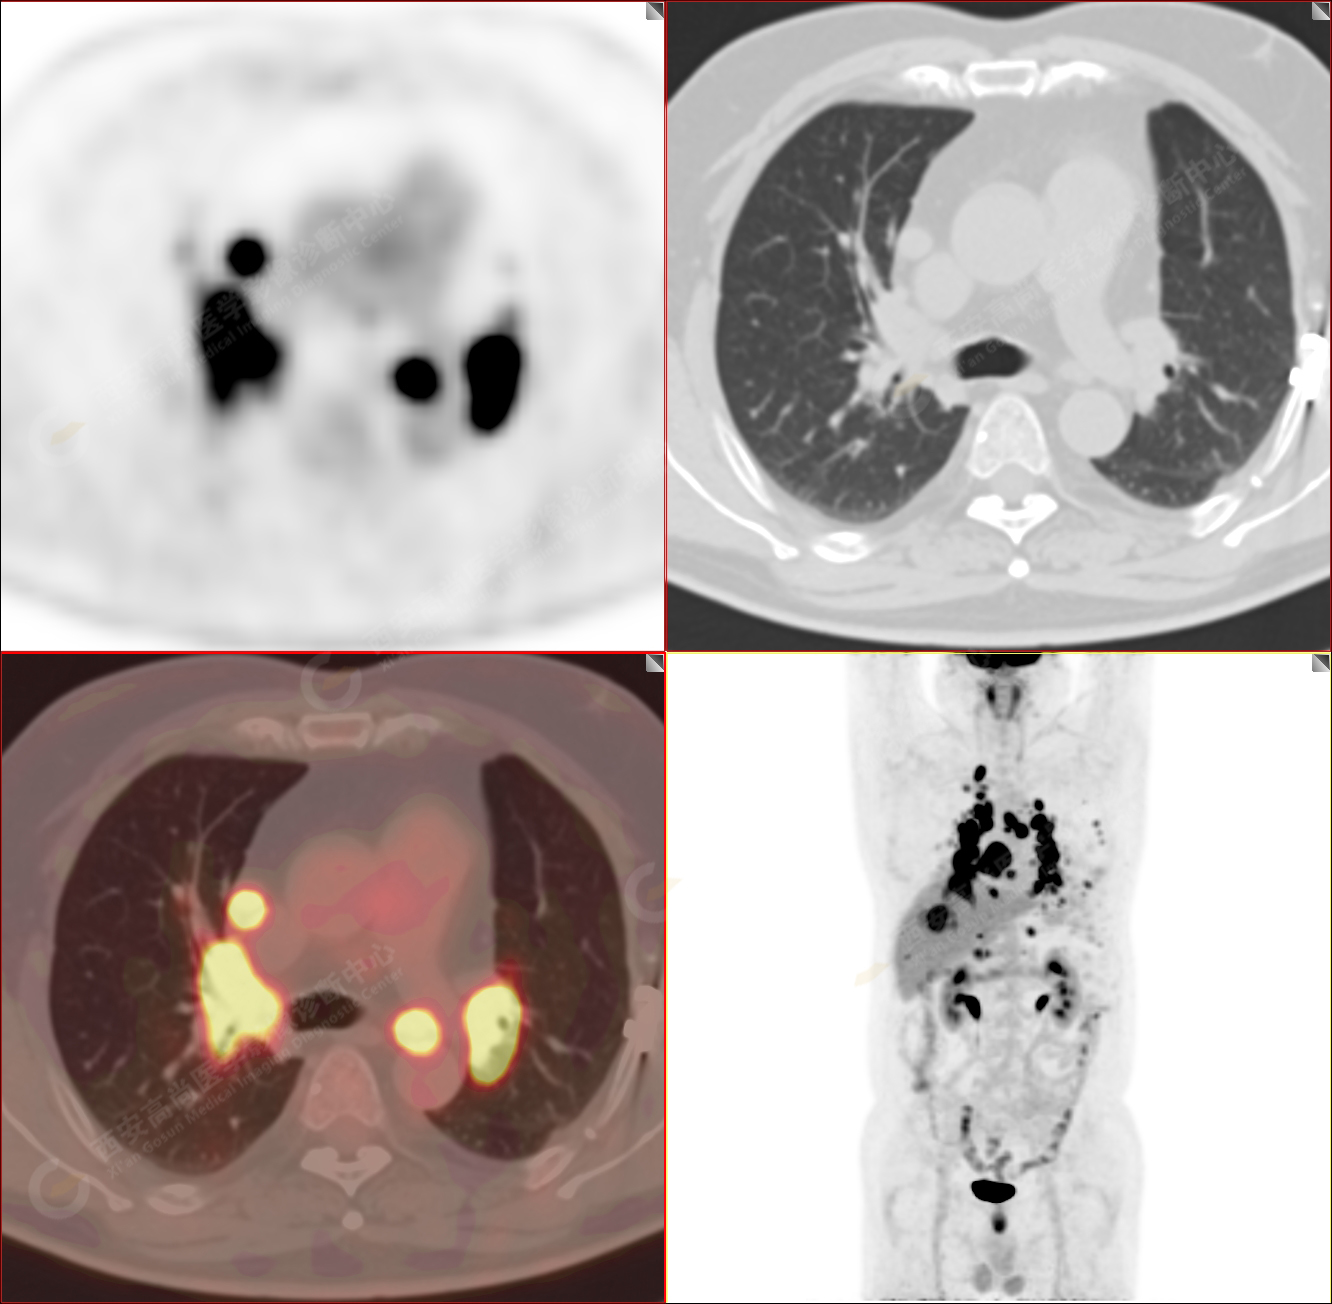

男性,53歲,頭暈半月入院,CT發(fā)現(xiàn)肺內(nèi)腫塊,雙肺多發(fā)大小不等實性及粟粒樣結(jié)節(jié),雙肺門及縱隔多發(fā)腫大淋巴結(jié)。病程中無發(fā)熱、胸悶氣及胸部不適。既往:左側(cè)肋骨外傷史。

PET/CT圖像